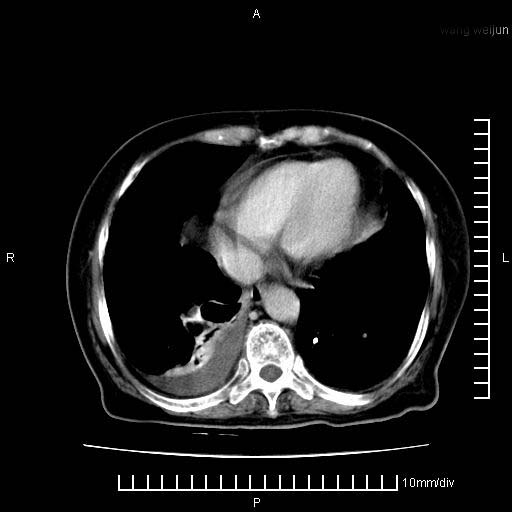

3。右胸腔积液,伴右肺下叶部分萎陷。

1)考虑胰腺癌并胰腺假性囊肿形成。2)肝内低密度灶,不排除转移。3)右肾盂积水。4)腹水。5)右侧胸腔积液并右肺下叶部分膨胀不全。

考虑胰腺ca伴腹膜腔转移、肝左叶转移、右肾积水。右胸腔积液。

考虑胰腺ca伴腹膜腔转移、肝左叶转移、右肾积水。右胸腔积液。支持